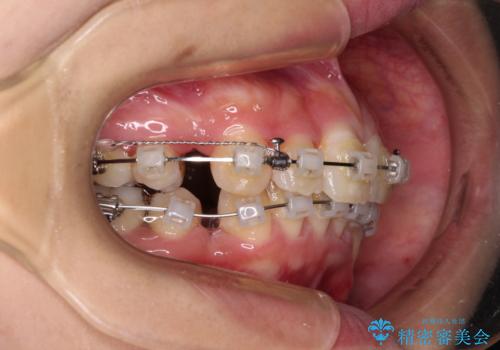

- クリアブラケット

- 3年4ヶ月

- 30回以上